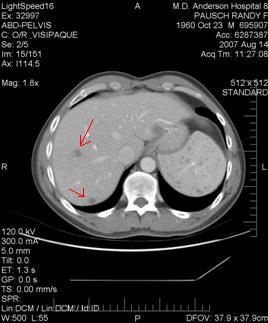

For those of you familiar with boxing, I would describe the weeks since my heart & kidney failure to be a "standing eight count." I got knocked down pretty good and needed time to gather myself. Now I'm back on my feet; still a little wobbly, but ready to engage in the fight again. Yesterday's CT and MRI scans showed that I've added a new, 11th tumor (small), and that a few of my original 10 tumors have grown, but only negligibly so. My biggest tumor is about 2.5cm in diameter. Given that I've been off chemo for six weeks, this was jumping-up-and-down good news, for two reasons: 1) It means the cancer has not grown like craxy, a big fear since stopping chemo. 2) Since all my tumors are in my liver, that means certain liver-specific treatments are possible. I'm typing this from a recovery room; I just had a biopsy taken of my tumor tissue; that will be sent to TGEN in arizona, where they will run some tests to see if they can identify which chemotherapy drugs might be most effective on my particular tumors. My next step will probably be embolization with theraspheres; a liver specific treatment that has a very low rate of side effects, and won't make me feel crappy like systemic chemo does. The fight is rejoined; I've got much more energy now -- I hope to be back on the bike in a week or so. |